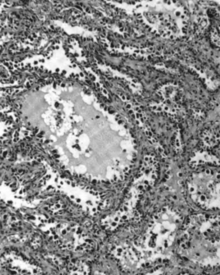

Micrograph of a mucinous ovarian carcinoma stained by H&E. | |

Mucinous tumors include mucinous adenocarcinoma and mucinous cystadenocarcinoma.[18]

Mucinous adenocarcinoma

Mucinous adenocarcinomas make up 5–10% of epithelial ovarian cancers. Histologically, they are similar to intestinal or cervical adenocarcinomas, and are often actually metastases of appendiceal or colon cancers. Advanced mucinous adenocarcinomas have a poor prognosis, generally worse than serous tumors, and are often resistant to platinum chemotherapy, though they are rare.[18]